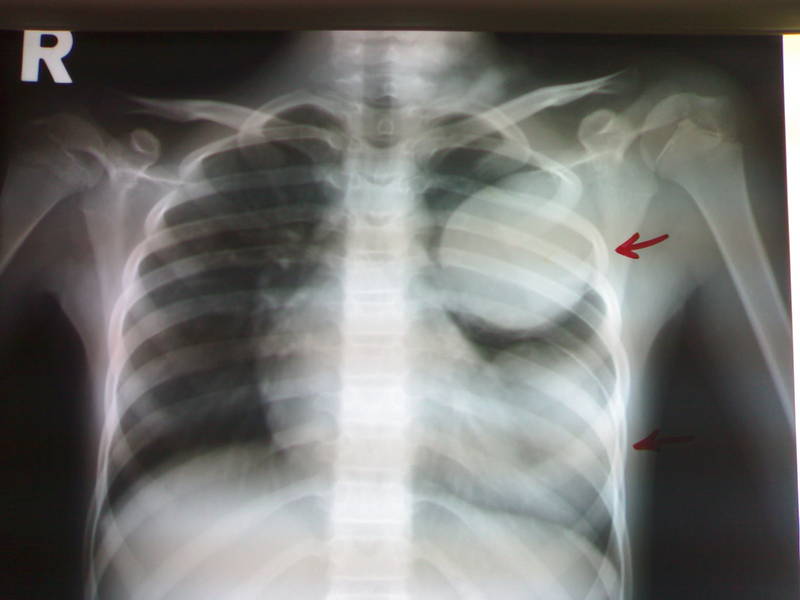

Паразитирование личинок в лёгких может быть выявлено флюорографически в виде так называемых — «летучего» инфильтрата — синдром Лёффлера.

Паразитирование гельминтов в лёгких может приводить к различным расстройствам — пневмонии, кашле, астме, кровоизлияния, отёки, возможна асфиксия, и другие исходы.